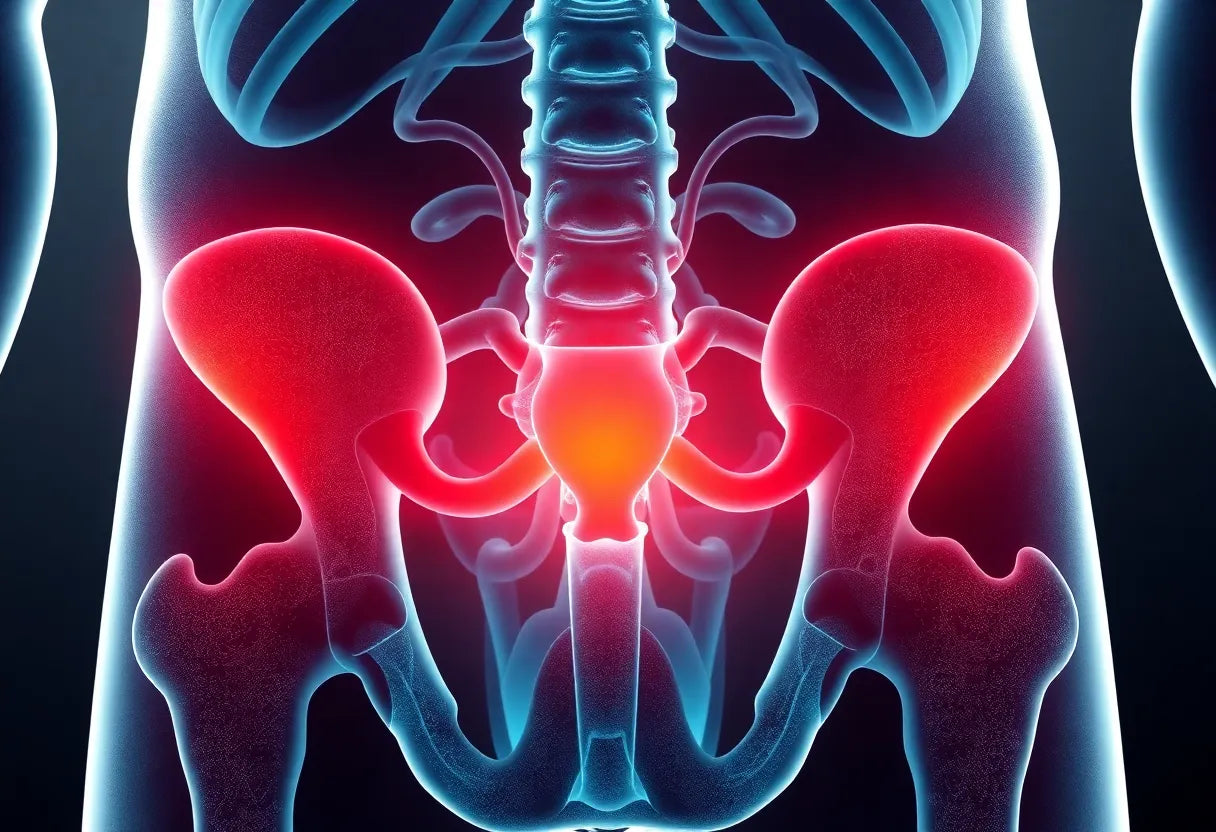

Een veelvoorkomend symptoom is uitstralende pijn, die optreedt wanneer de uitpuilende tussenwervelschijf druk uitoefent op nabijgelegen zenuwen. Dit kan leiden tot pijn die uitstraalt naar de benen, billen of zelfs de voeten. Naast pijn kunnen ook een drukkend gevoel, gevoelloosheid en verminderde kracht in de benen optreden. Deze symptomen kunnen de mobiliteit en het dagelijks functioneren aanzienlijk beïnvloeden.

Om te begrijpen hoe een hernia ontstaat, is het nuttig om de basisanatomie van de wervelkolom te kennen. De wervelkolom bestaat uit een reeks botten genaamd wervels, die worden gescheiden door tussenwervelschijven. Deze schijven fungeren als schokdempers en maken beweging mogelijk. Een hernia treedt op wanneer de zachte kern van een schijf door een scheur in de buitenste laag naar buiten puilt, waardoor druk op de zenuwen ontstaat. Dit kan leiden tot de symptomen die we eerder hebben besproken.